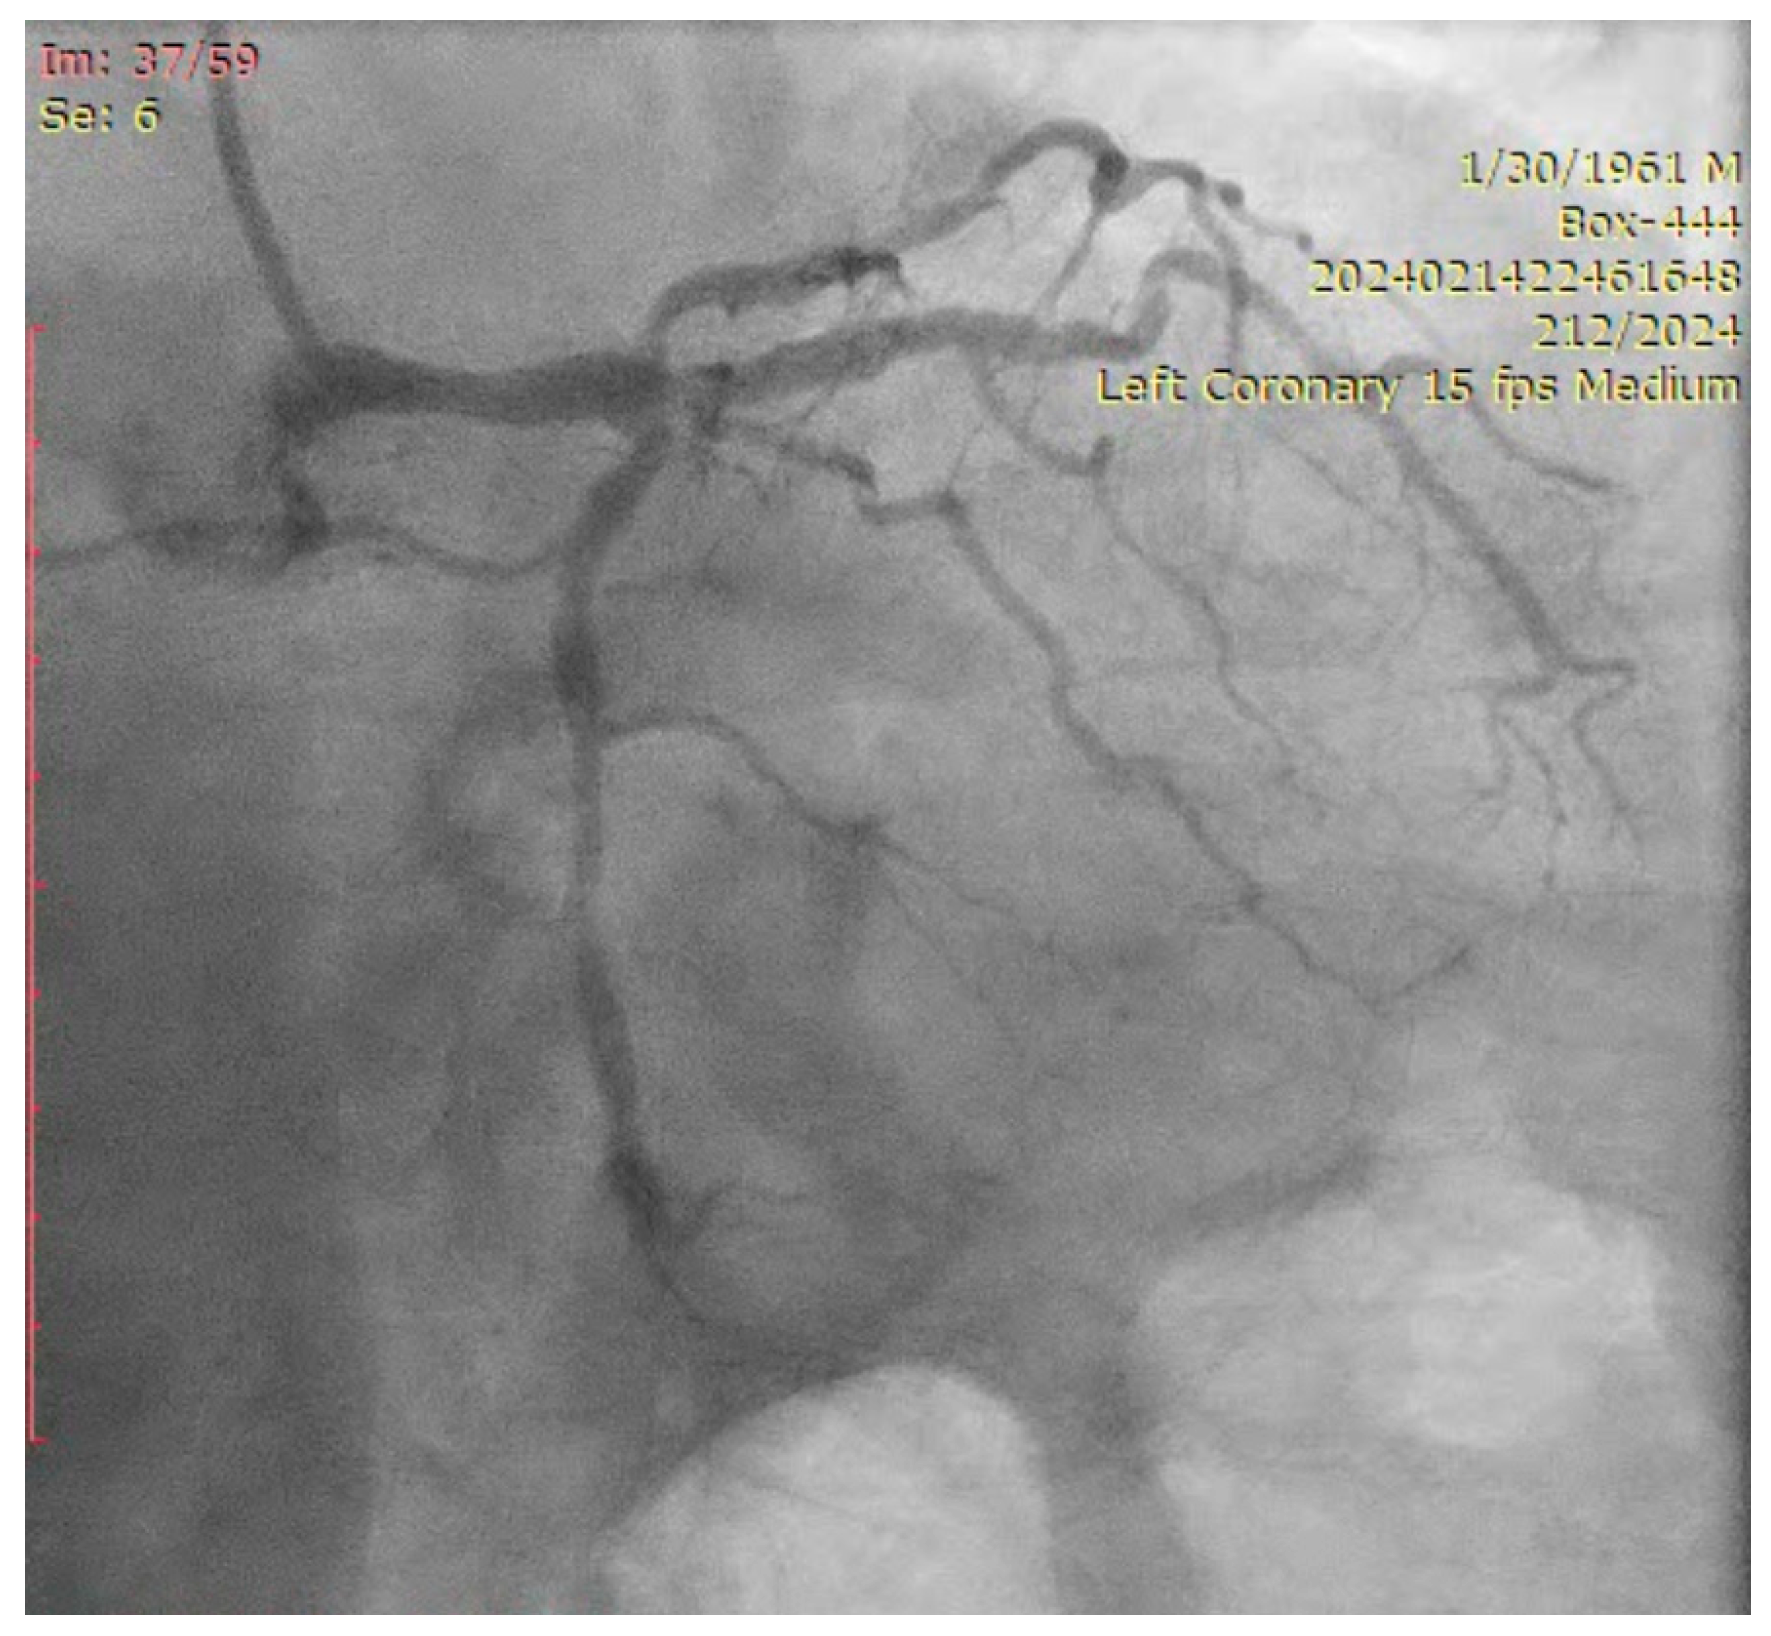

The ostium of left anterior descending artery (LAD) presented a 75% stenotic lesion, with the proximal segment displaying a 90% lesion (Figure 3). The left circumflex artery (LCX) revealed a 75% stenotic lesion of the ostium and tapered disease of its distal segment with areas of ectasic disease, with the ostium of the ramus intermedius (RI/RM) showing a 75% lesion (modified Medina classification 0-1-1-1 [4]) (Figure 4, Figure 5, Figure 6, Figure 7, Figure 8, Figure 9 and Figure 10).

Figure 5.

Left coronary artery—RM(LAO caudal). Green arrow and square—ostium of RM.